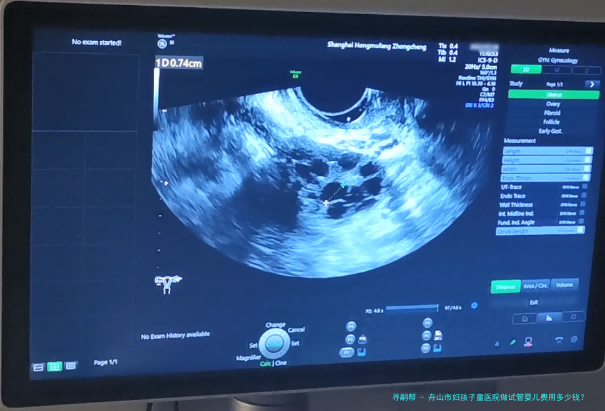

希望拥有本人的宝宝,但因为诸多原因无从自然受孕,试管婴儿就成为无数家庭的曙光。舟山市作为一个享有许多优质医疗机构之处,也提供着完备的试管婴儿服务。哪样舟山市妇孩子童医院做试管婴儿费用多少钱?成功率怎样呢?

舟山市妇孩子童医院是一家集医疗、教学、科研为一体的综合性三级妇产专科医院。医院成立于1958年,拥有先进的医疗配备和专业的医护集体,专心于为女性及儿童提供优质的医护服务。医院一向坚持“以人为核心”的观念,承继“精良、规范、高成效”的服务宗旨,为患者提供全面性、个体化的服务。

舟山市妇孩子童医院试管婴儿费用

| 项目 | 费用 |

| 检查费用(包括血常规、激素检测等) | 约6,000元 |

| 促排卵药物 | 约20,000元 |

| 助孕手术费 | 约10,000元 |

| 胚胎培养费 | 约5,000元 |

| 移植手术费 | 约8,000元 |

| 基因检测费用 | 约10,000元 |

舟山市妇孩子童医院的试管婴儿成功率在百分之六十五左右,详细的成功率还会根据患者的身体状态、年龄等因素有所差异。